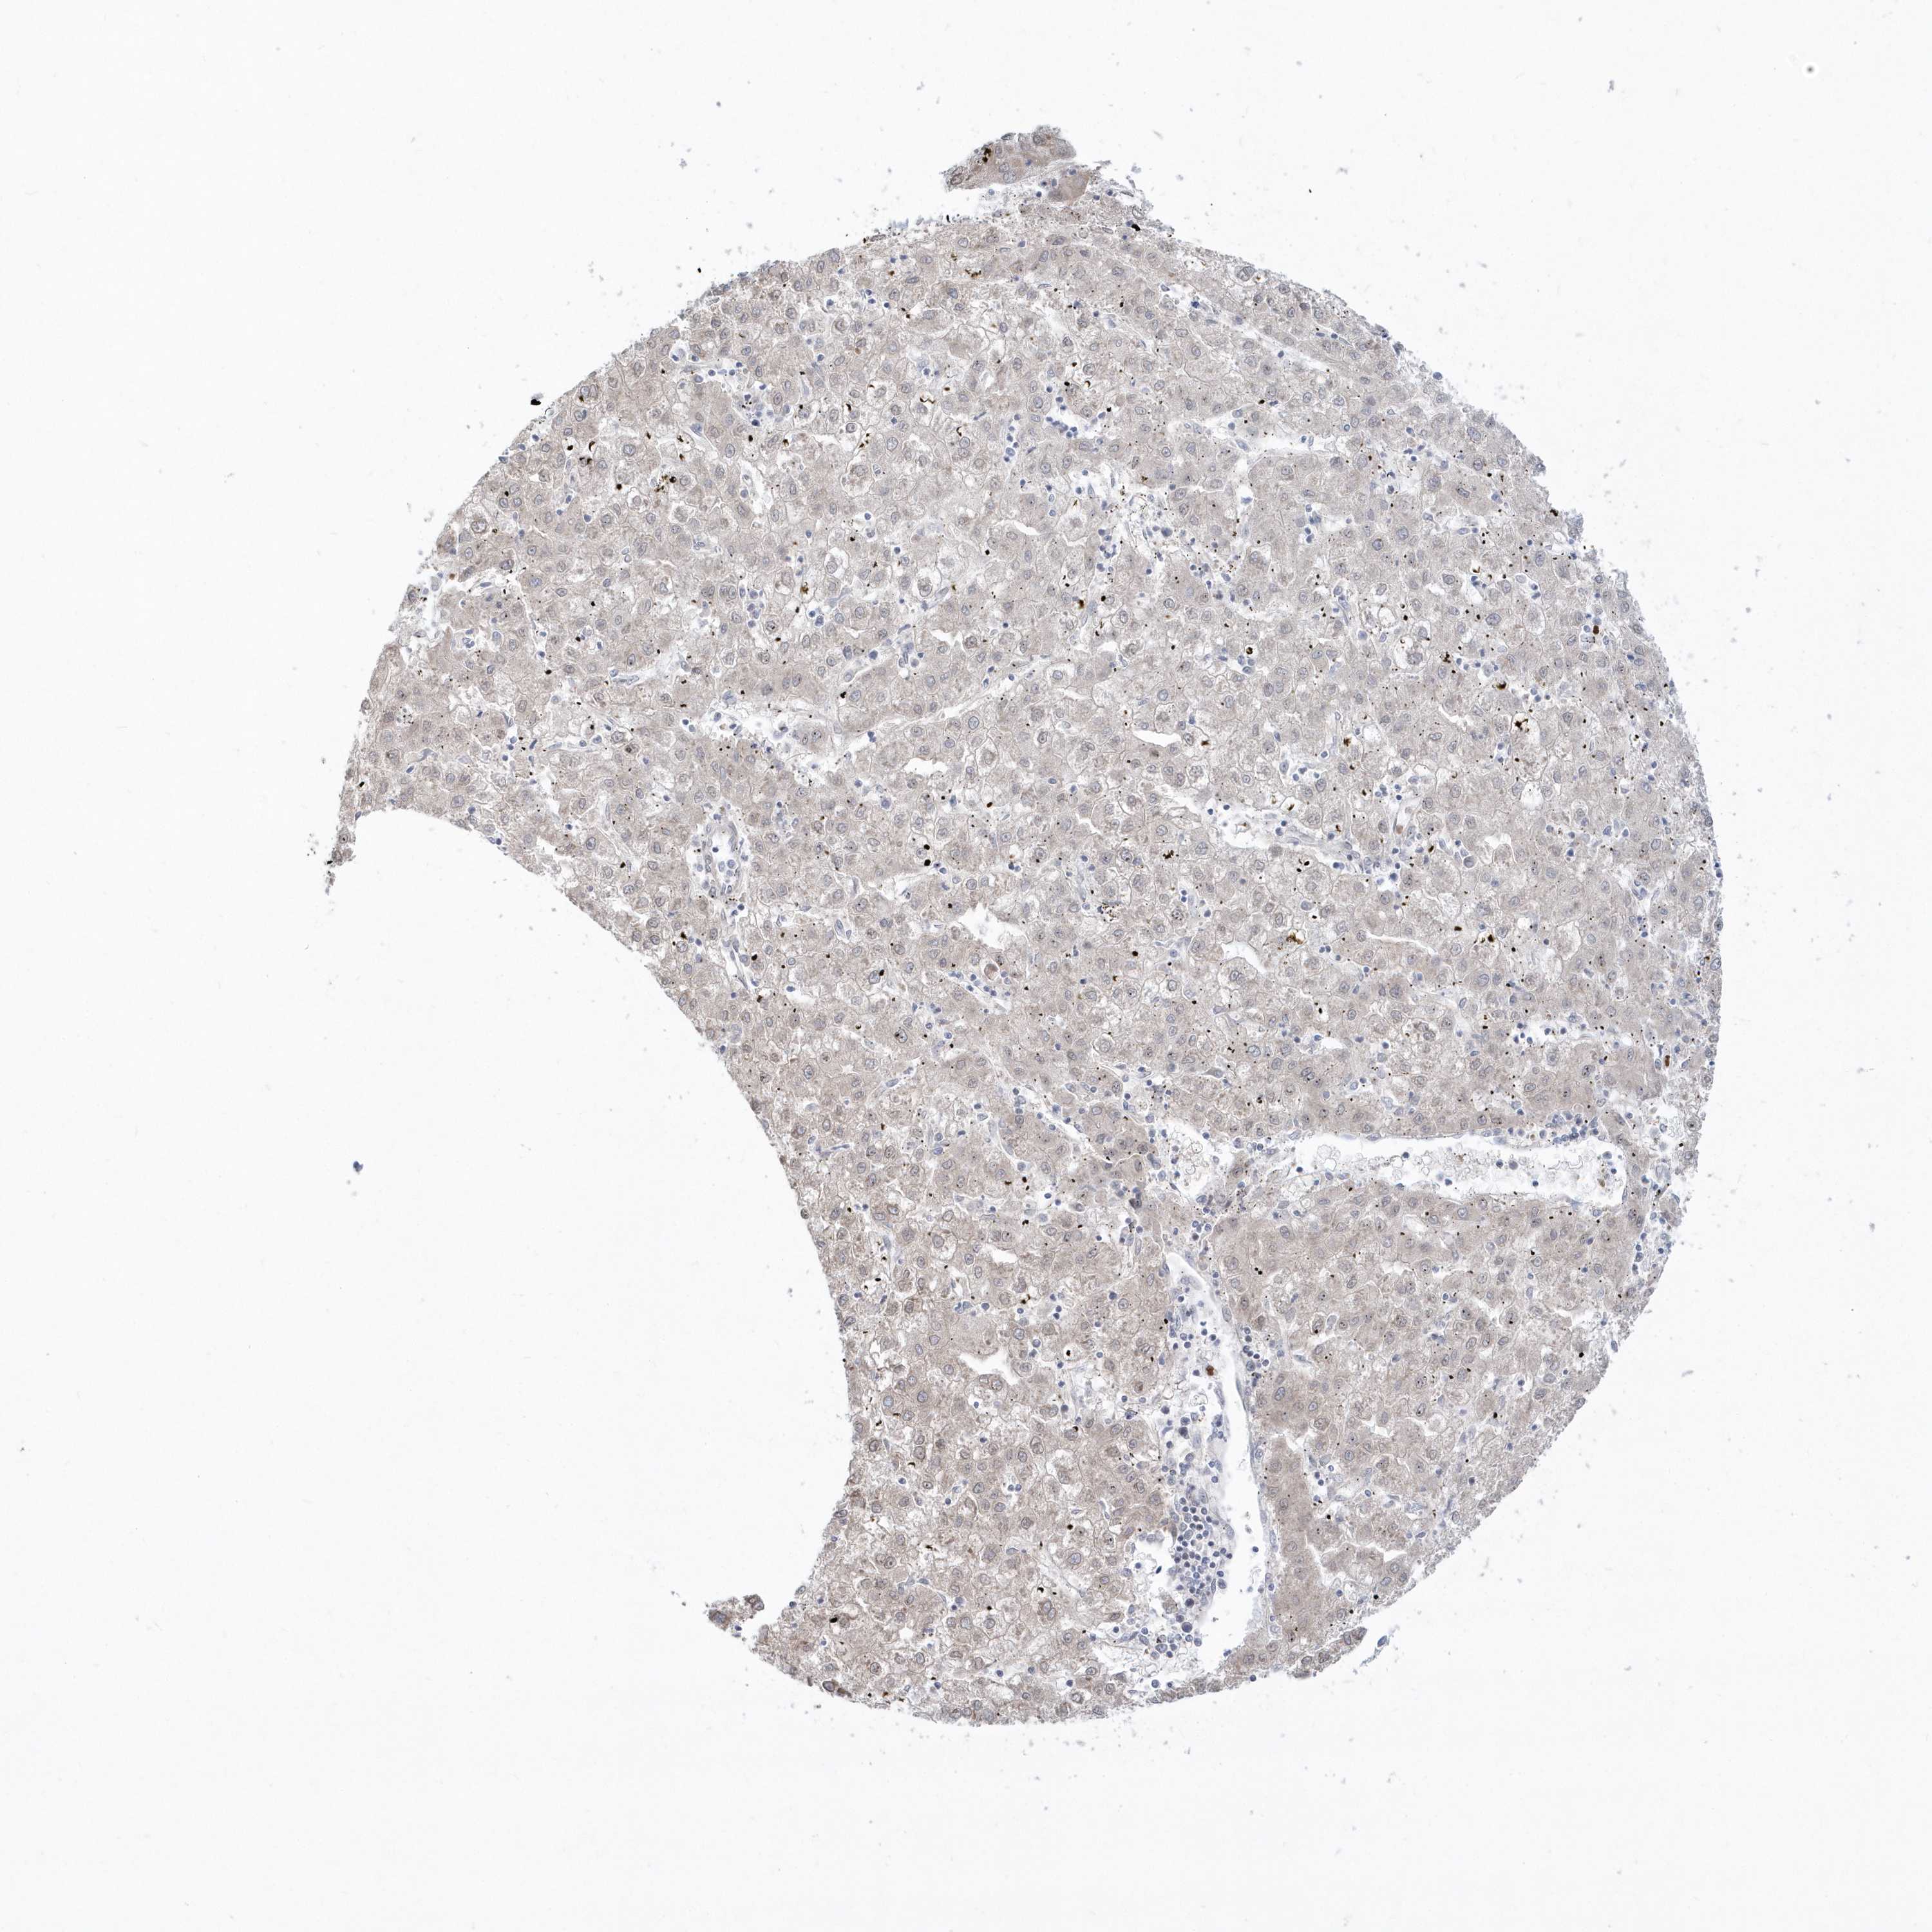

LIVER CANCER - Protein expressioni

A mouse-over function shows sample information and annotation data. Click on an image to view it in a full screen mode. Samples can be filtered based on level of antibody staining by selecting one or several of the following categories: high, medium, low and not detected. The assay and annotation is described here.

Note that samples used for immunohistochemistry by the Human Protein Atlas do not correspond to samples in the TCGA dataset.

Antibody stainingi

Antibody staining in the annotated cell types in the current human tissue is reported as not detected, low, medium, or high, based on conventional immunohistochemistry profiling in selected tissues. This score is based on the combination of the staining intensity and fraction of stained cells.

Each image is clickable and will lead to virtual microscopy that enables deeper exploration of all samples and also displays staining intensity scores, fraction scores and subcellular localization as well as patient and tissue information for each sample.

Antibody HPA036160

Staining

High

Medium

Low

Not detected

Intensity

Strong

Moderate

Weak

Negative

Quantity

>75%

75%-25%

<25%

None

Location

Nuclear

Cytoplasmic/membranous

Cytoplasmic/membranous,nuclear

Cholangiocarcinoma

Carcinoma, Hepatocellular, NOS